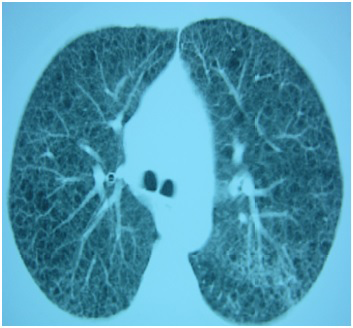

Figure 1: Lung TC where bullae and cystic lesions can be observed.

figure 1